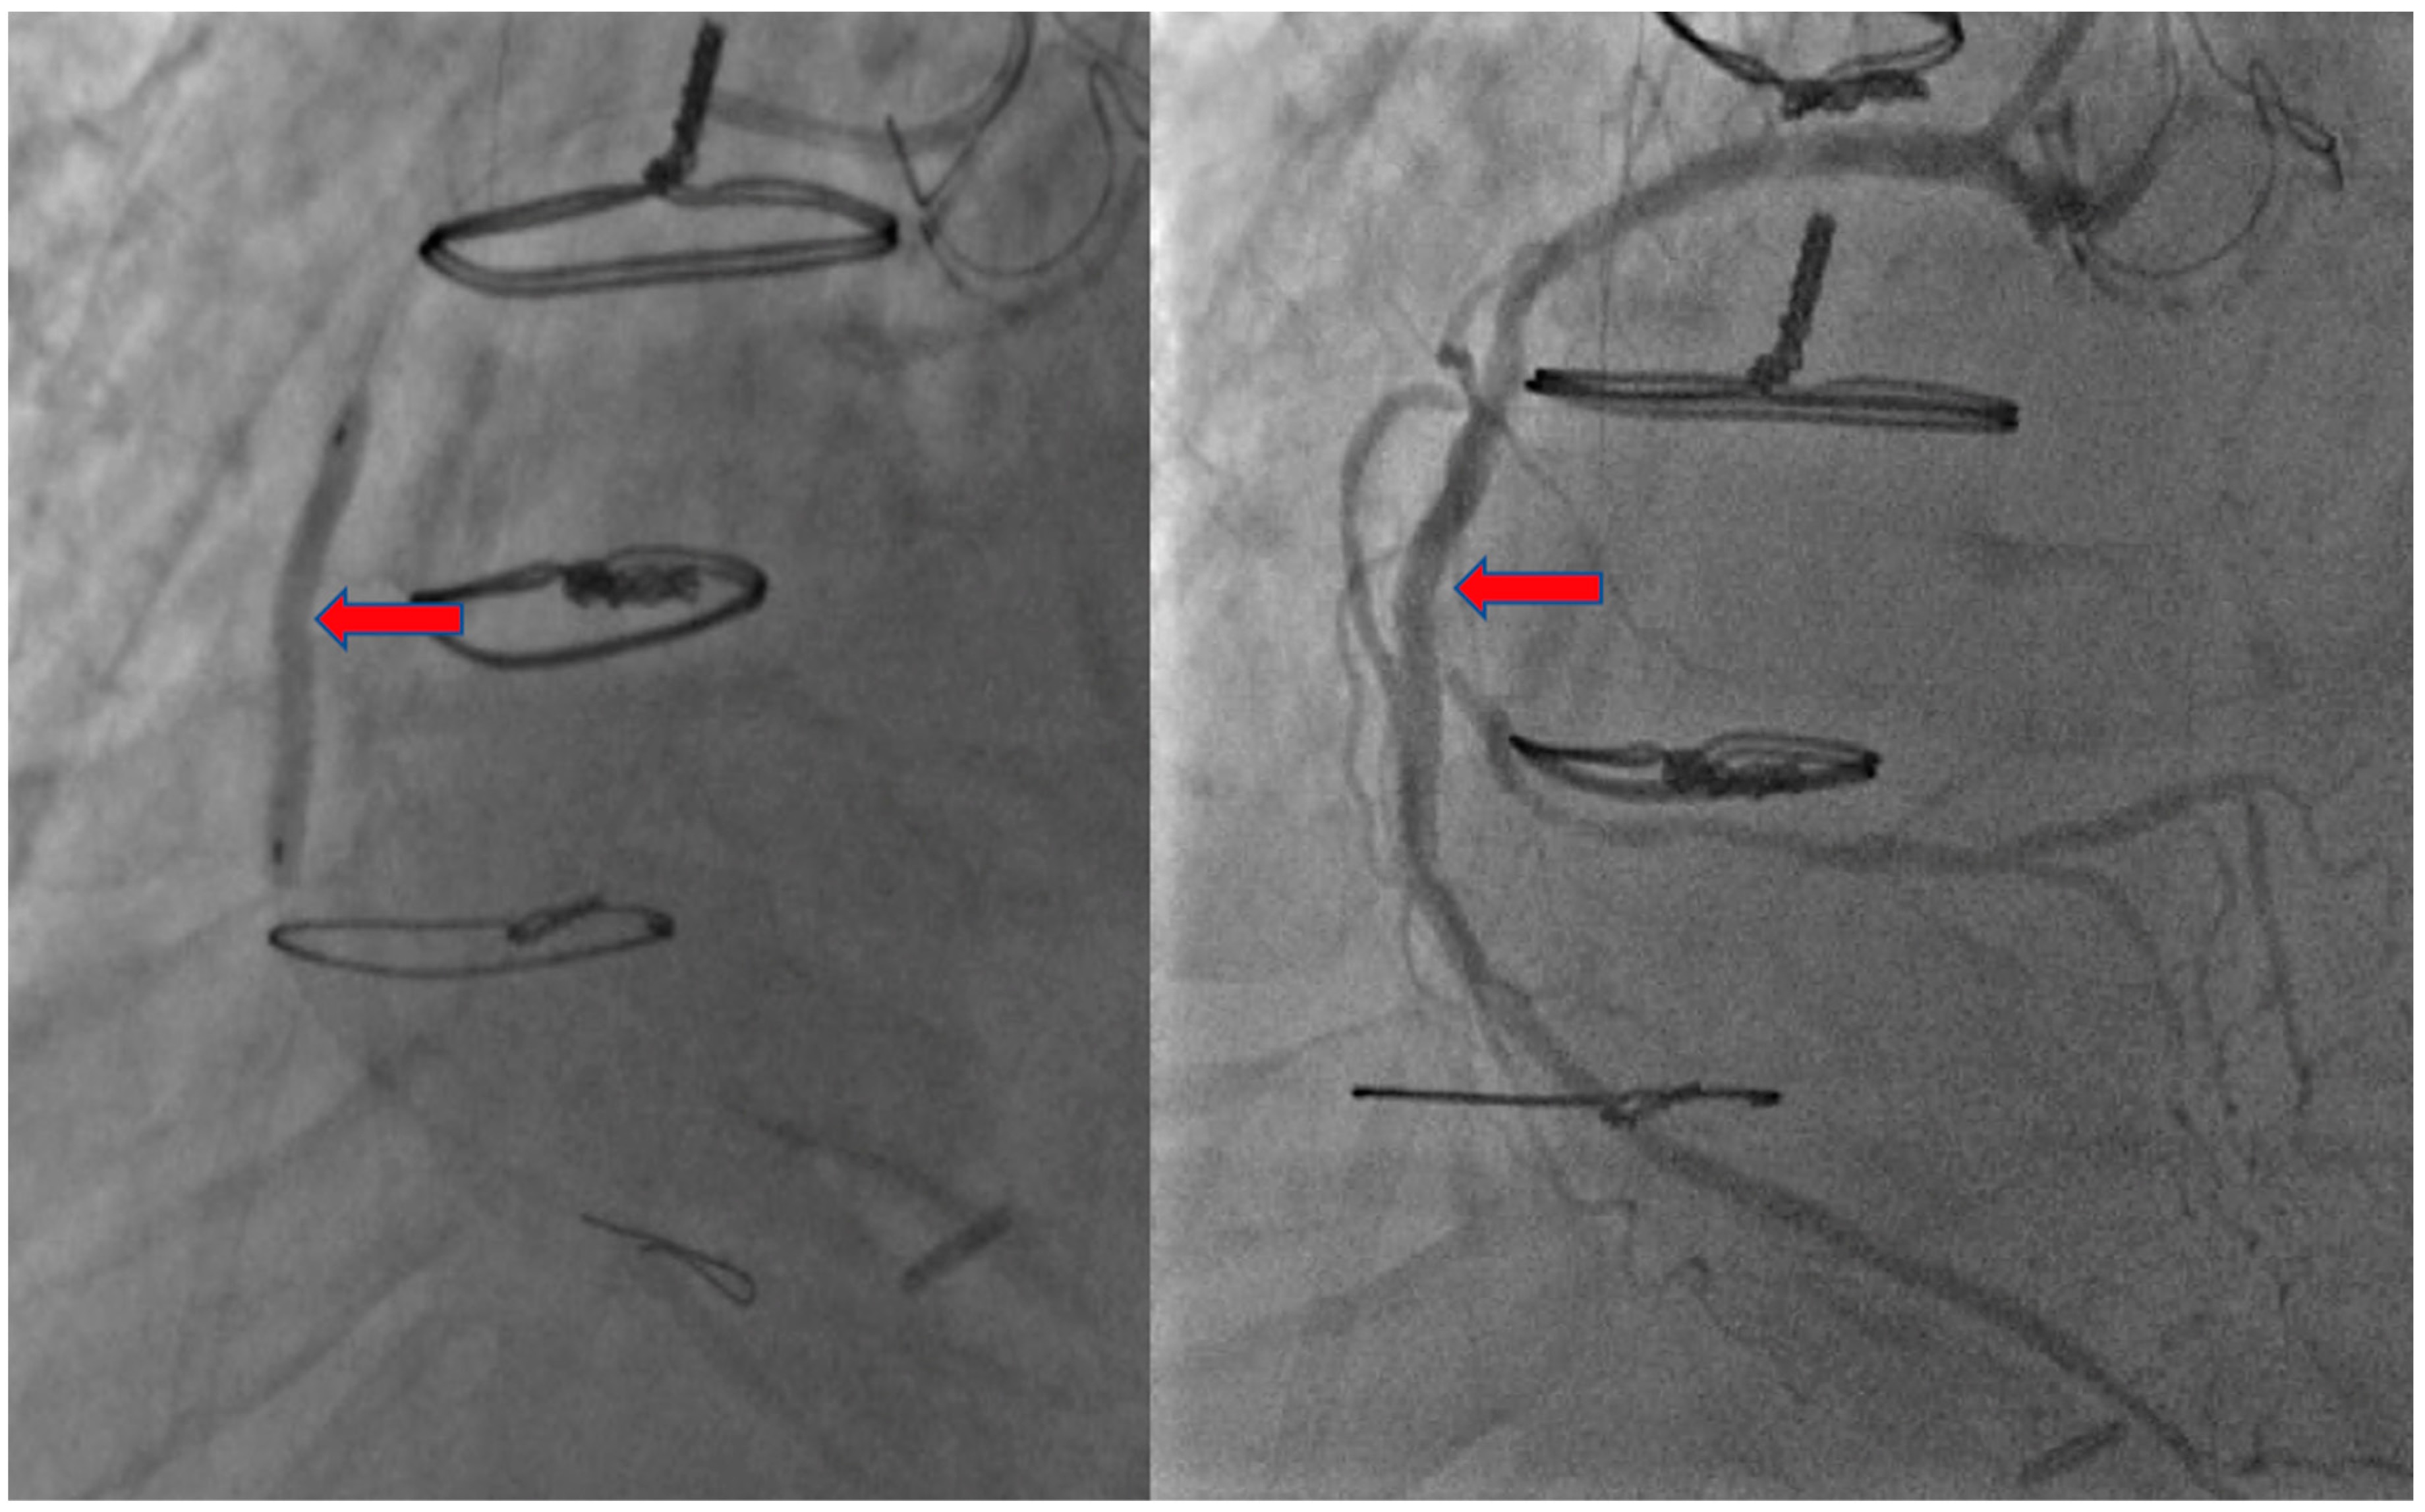

2. Case Presentation